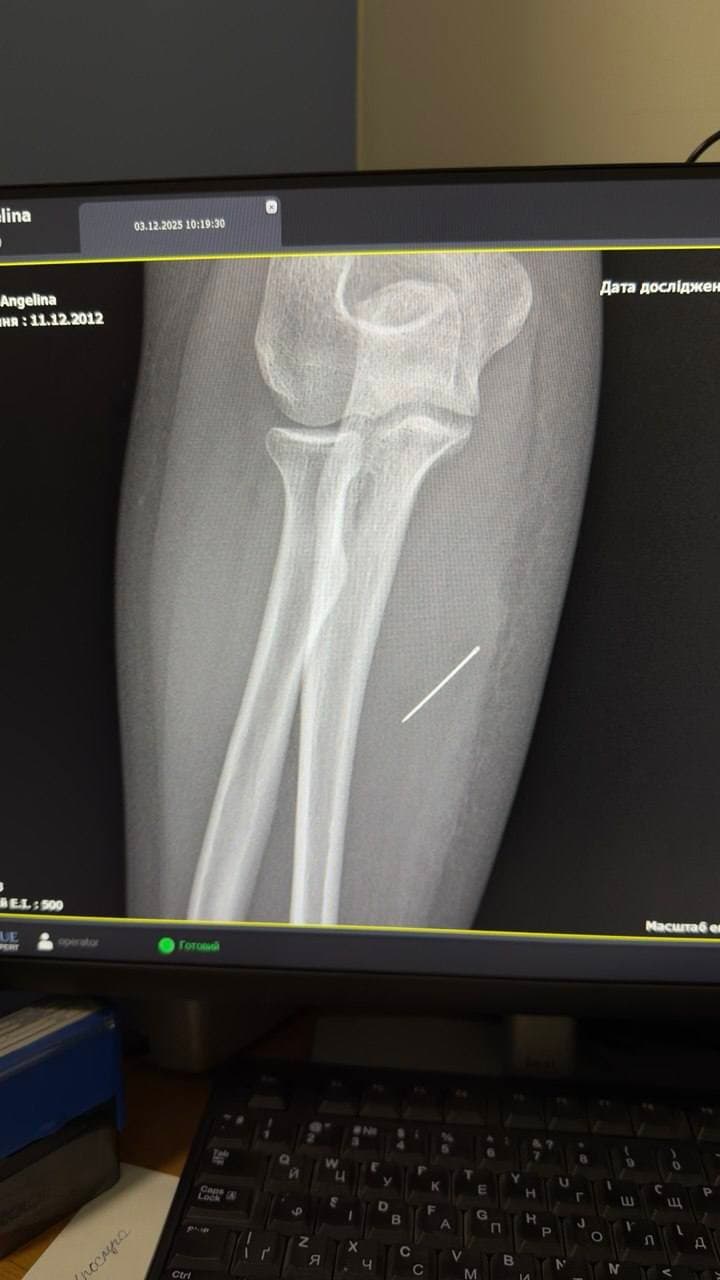

Під час додаткового обстеження лікарі з’ясували, що за тиждень голка просунулася глибше і зайшла в м’яз під кутом 45 градусів. Медики наголошують, що подальша міграція могла призвести до ушкодження судин або нервових закінчень.

Операцію проводили з використанням рентген-навігації ЕОП. Критично важливо було витягнути голку точно за траєкторією її входження, аби уникнути її перелому та ускладнення подальшого пошуку уламків у м’язових тканинах. Стороннє тіло вдалося вилучити через невеликий розріз без ускладнень.